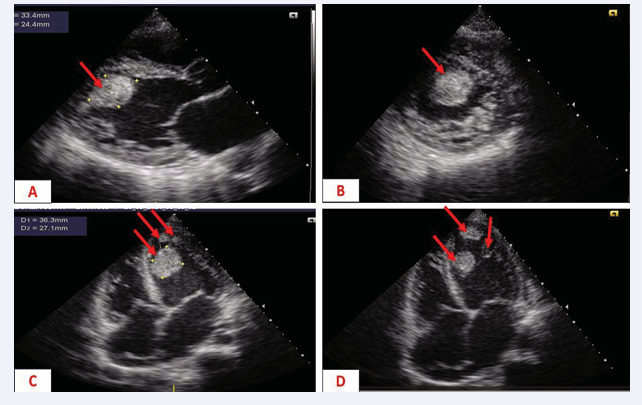

The patient was 24 years old, primigravida, primiparous, with no previous pathological history, and was referred for New York Health Association stage IV dyspnoea. This dyspnoea began one week after vaginal delivery, followed by a progressive worsening, becoming orthopnoic, associated with moderate precordialgia and oedema of the lower limbs. On physical examination, the patient’s general condition was stage III (WHO performance status), her conjunctivae and mucous membranes were pale, her blood pressure was 130/88 mmHg, she had congestive heart failure, and she had a 3/6 murmur of mitral insufficiency. This clinical picture led to the suspicion of peripartum cardiomyopathy, valvularheartdiseaseoradecompensated anaemic heart. The electrocardiogram showed regular sinus tachycardia. Doppler echocardiography showed dilatation of the left ventricle (diastolic diameter 57 mm), an altered left ventricular ejection fraction of 35%, and hypertrabeculation inside the left ventricle, which was very vascular on colour Doppler, with three trombi in the left ventricle (Figure 1).

Figure 1 Doppler echocardiogram showing A: para-sternal long-axis section, large intra-VG thrombus (red arrow) B: trans-ventricular short-axis paraspinal slice, large intra-GV thrombus (red arrow) C and D: apical 4-cavity slice, three intra-VG thrombi (red arrow)

Figure 1: Doppler echocardiogram showing

A: para-sternal long-axis section, large intra-VG thrombus (red arrow)

B: trans-ventricular short-axis paraspinal slice, large intra-GV thrombus (red arrow)

C and D: apical 4-cavity slice, three intra-VG thrombi (red arrow)